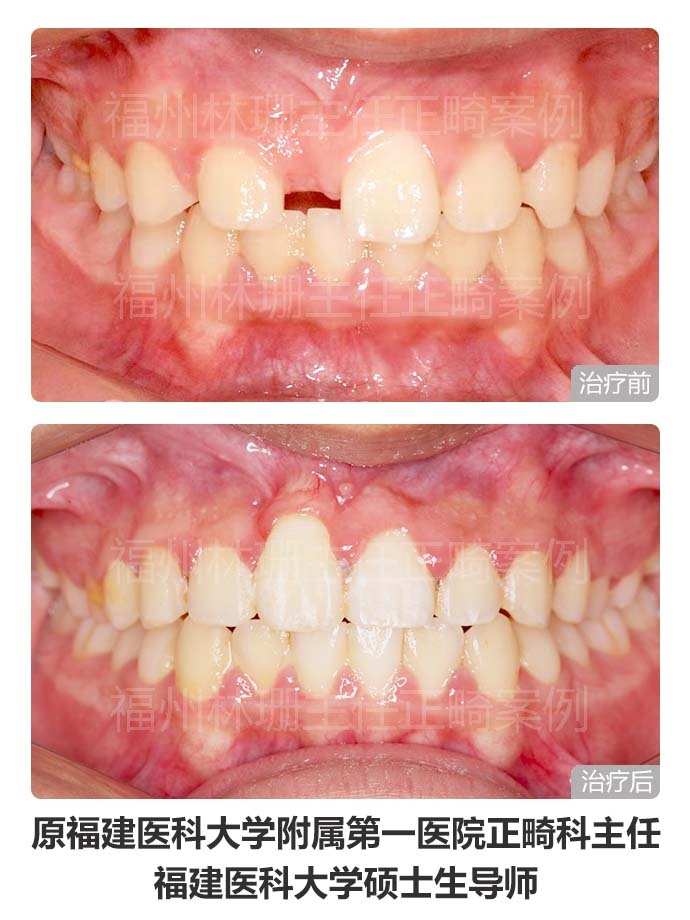

患者主诉替牙后发现上门牙未萌出,前来就诊。 检查双侧面部基本对称,侧貌直。口内检查示右上中切牙未萌出,右上侧切牙与左上中切牙存间隙。上牙列稍不齐。上中线右偏2mm,下中线正。cbct示:右上中切牙倒置阻生,合方见一多生牙。 考虑患者侧貌可,牙列拥挤度不大,且上牙列存有间隙,可通过适当扩弓拓展间隙。因此选择非拔牙矫正,利用扩弓提供的间隙牵引埋伏阻生的右上中切牙,排齐整平上下牙列,调整中线。 矫正后埋伏阻生的右上中切牙已牵引到位。上下牙列整齐,上下牙弓形态佳,上下牙弓匹配;上下前牙覆合覆盖良好,后牙咬合关系良好,上下中线正,同时维持良好侧貌。